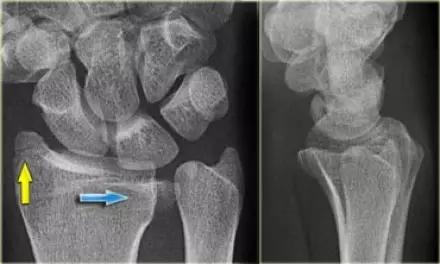

5. Chauffeur 骨折/ Hutchinson 骨折

桡骨干的斜形骨折,早期有机械性弯曲,进而通过逆性外力造成的斜形骨折。指桡骨茎突受舟骨撞击的剪切骨折形成带关节面的三角形骨折。